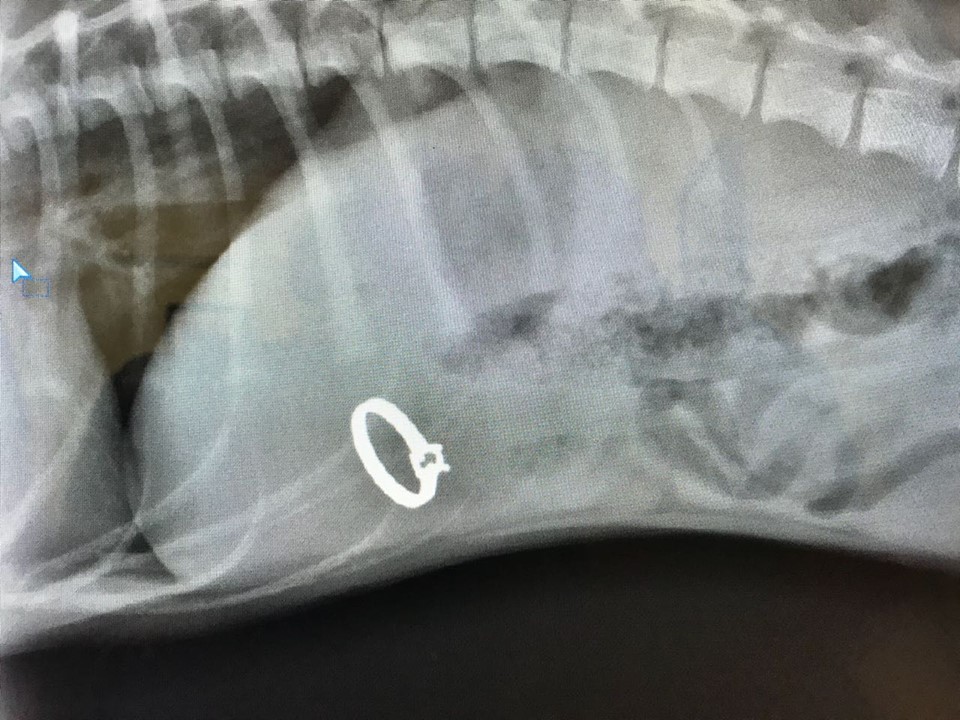

Cape Town pup ate mom's wedding ring and got slightly famous! Dog Swallowed Jewelry Many pieces of jewelry are sharp and can cut up the inside of your dog’s digestive system. Discovering that your dog has swallowed a ring can be a cause for concern. String, thread (with or without the. Luckily, most metals that are used in making jewelry, such as gold and silver, are generally nontoxic and shouldn’t pose any poisoning risk.. Dog Swallowed Jewelry.

Dog Swallows Owner's Engagement Ring, Comes Back 'Good As New' Dog Swallowed Jewelry Many pieces of jewelry are sharp and can cut up the inside of your dog’s digestive system. Discovering that your dog has swallowed a ring can be a cause for concern. What to do if your dog swallows a ring? However, it’s important to stay calm and take immediate. Whole toys or parts of toys, jewelry, coins, pins, erasers, and. Dog Swallowed Jewelry.